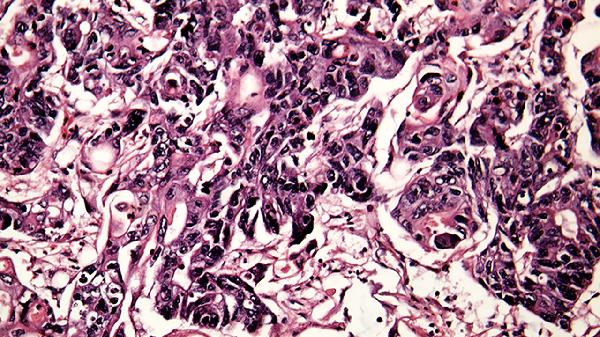

肺纤维化是肺部组织受损后异常修复形成的瘢痕组织,属于间质性肺疾病;而癌症是细胞异常增殖形成的恶性肿瘤。一个是"结疤",一个是"长瘤",发病机制完全不同。

3、影像学特征

CT检查中,肺纤维化呈现网格状、蜂窝状改变;肺癌则表现为结节或肿块。专业医生通过影像学检查可以明确区分。